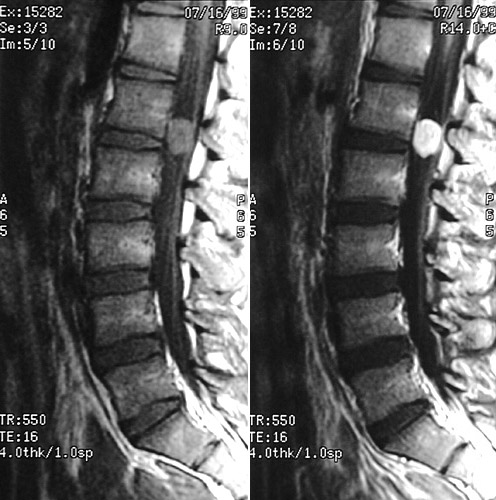

This MRI scan in sagittal view demonstrates a discrete, rounded schwannoma that nearly fills the spinal canal at the level of L2. The tumor mass is brightly enhancing with contrast.